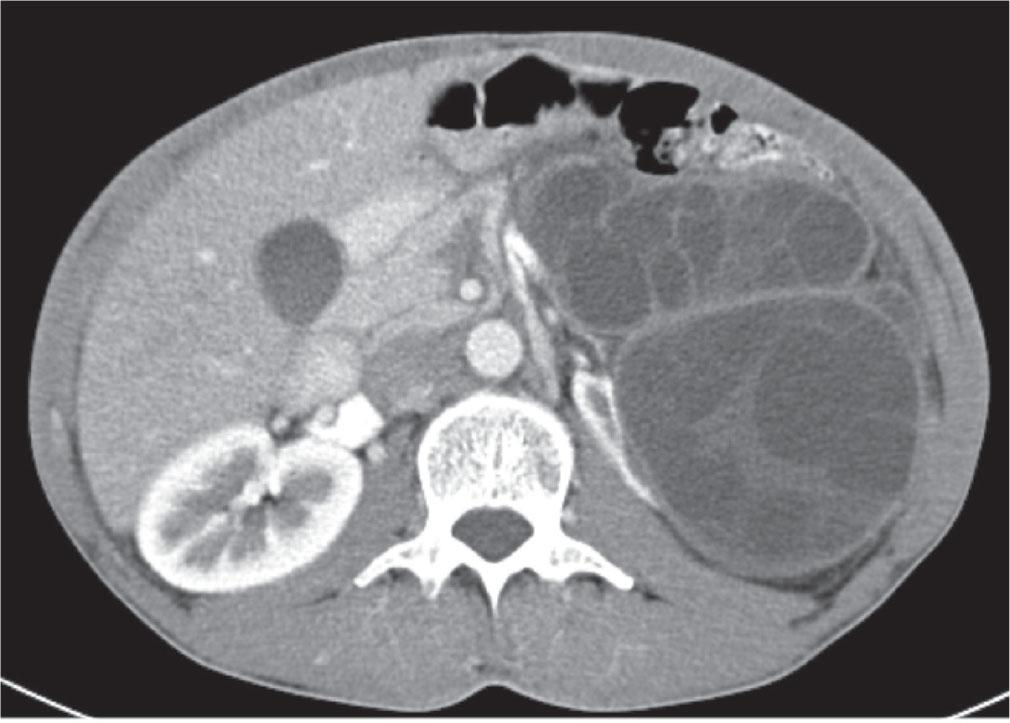

The follow-up imaging 12 months after surgery, including both ultrasound and MSCT scans, was reassuring, as it revealed no recurrence of lesions (Figure 3). In addition, antibody titres for Echinococcus granulosus measured four and 12 months after surgery showed a decreasing trend and reached the reference range 28 months after surgery (Table 1).

Postoperative contrast-enhanced MSCT of the abdomen and pelvis without cystic lesion 12 months after surgery